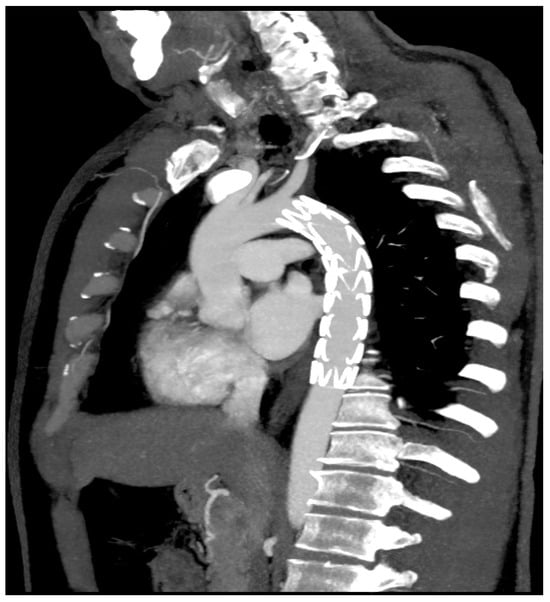

2. Case Presentation